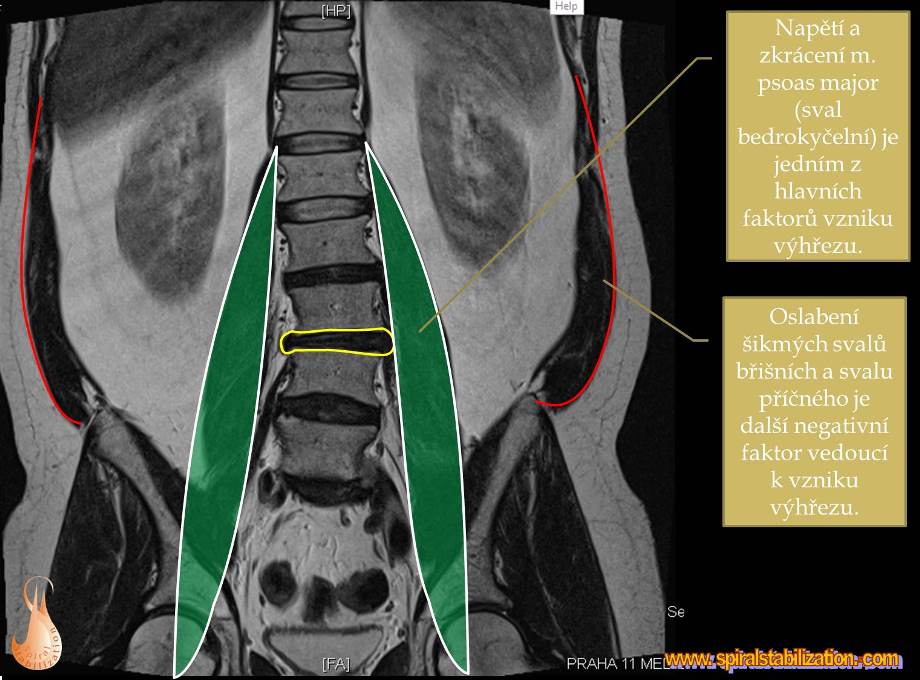

Základom liečby je aktivácia šikmých brušných svalov a relaxácia chrbta.

Výsledky hernia L3/L4